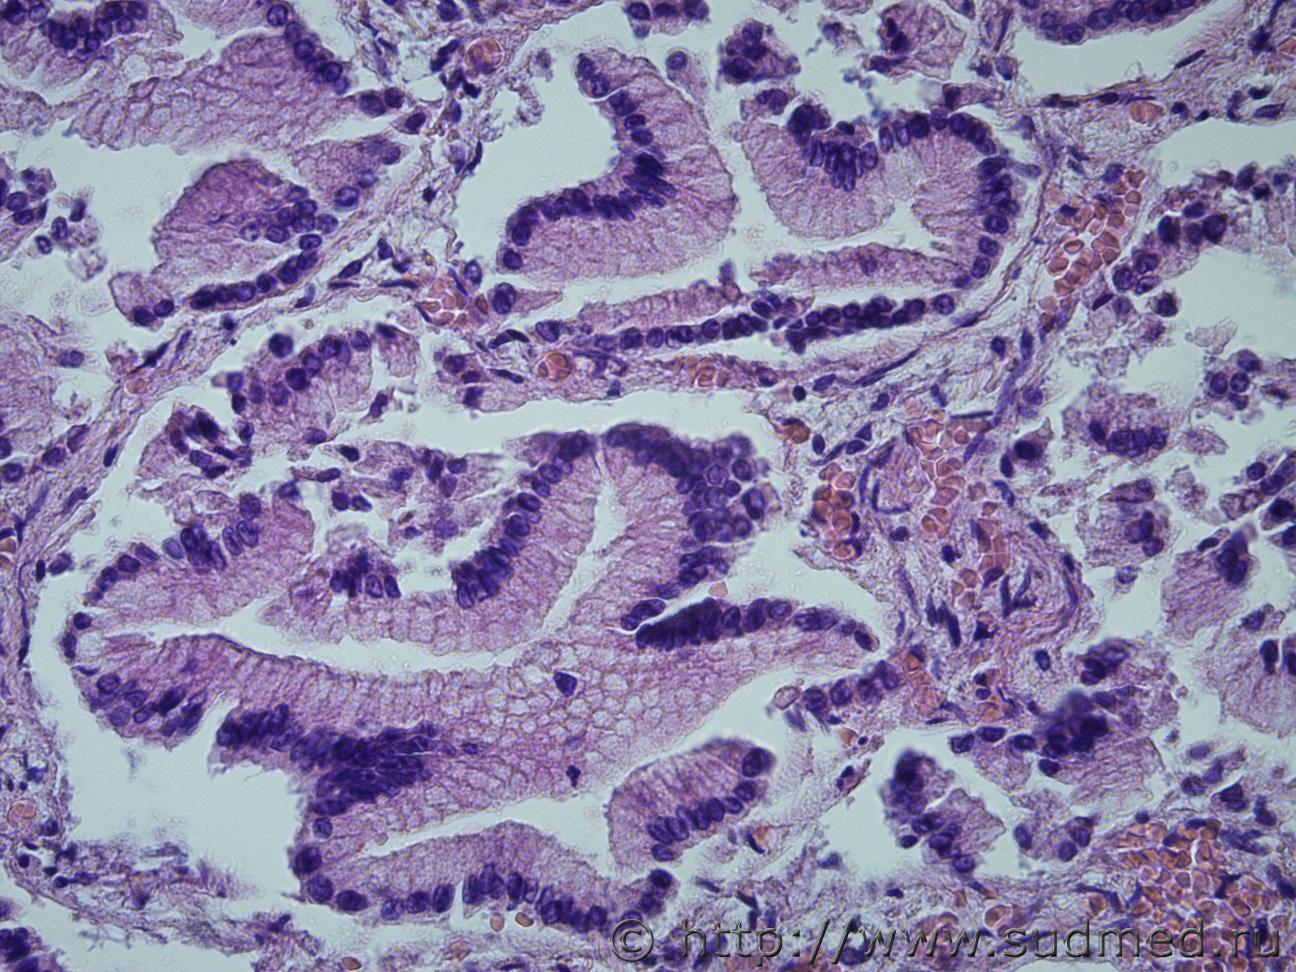

Ув. коллеги, сегодня в рубрике опухоль поджелудочной железы с метастазами в легкие. Муж, 80лет.

Легкие Судебная медицина - Прикрепленное изображениеСудебная медицина - Прикрепленное изображениеСудебная медицина - Прикрепленное изображение ПЖ Судебная медицина - Прикрепленное изображениеСудебная медицина - Прикрепленное изображениеСудебная медицина - Прикрепленное изображениеСудебная медицина - Прикрепленное изображение

Похоже на муцинозную цистаденокарциному? В легких очень красивый эпителий, а вот в поджелудочной такого эпителия очень мало(((

Похоже на муцинозную цистаденокарциному?

Да.

В гист.Акте печатайте без "цист". Просто, "муцинозная аденокарцинома".